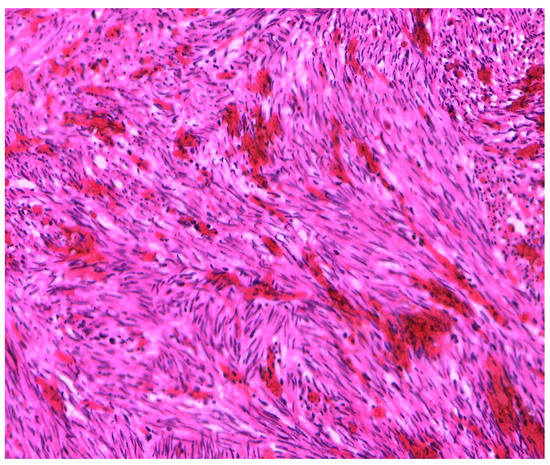

| Case Described by This Article | 50 | Yes | LPT Pfannenstiel | US + CT | 10 cm × 9 cm × 7 cm | Paraovarian mass | Mass only |